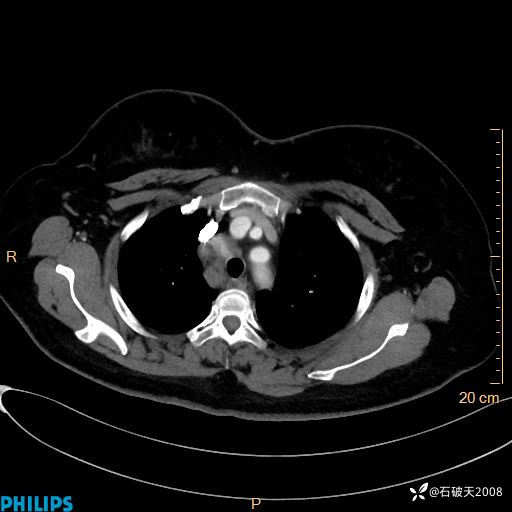

肺窗

纵隔窗